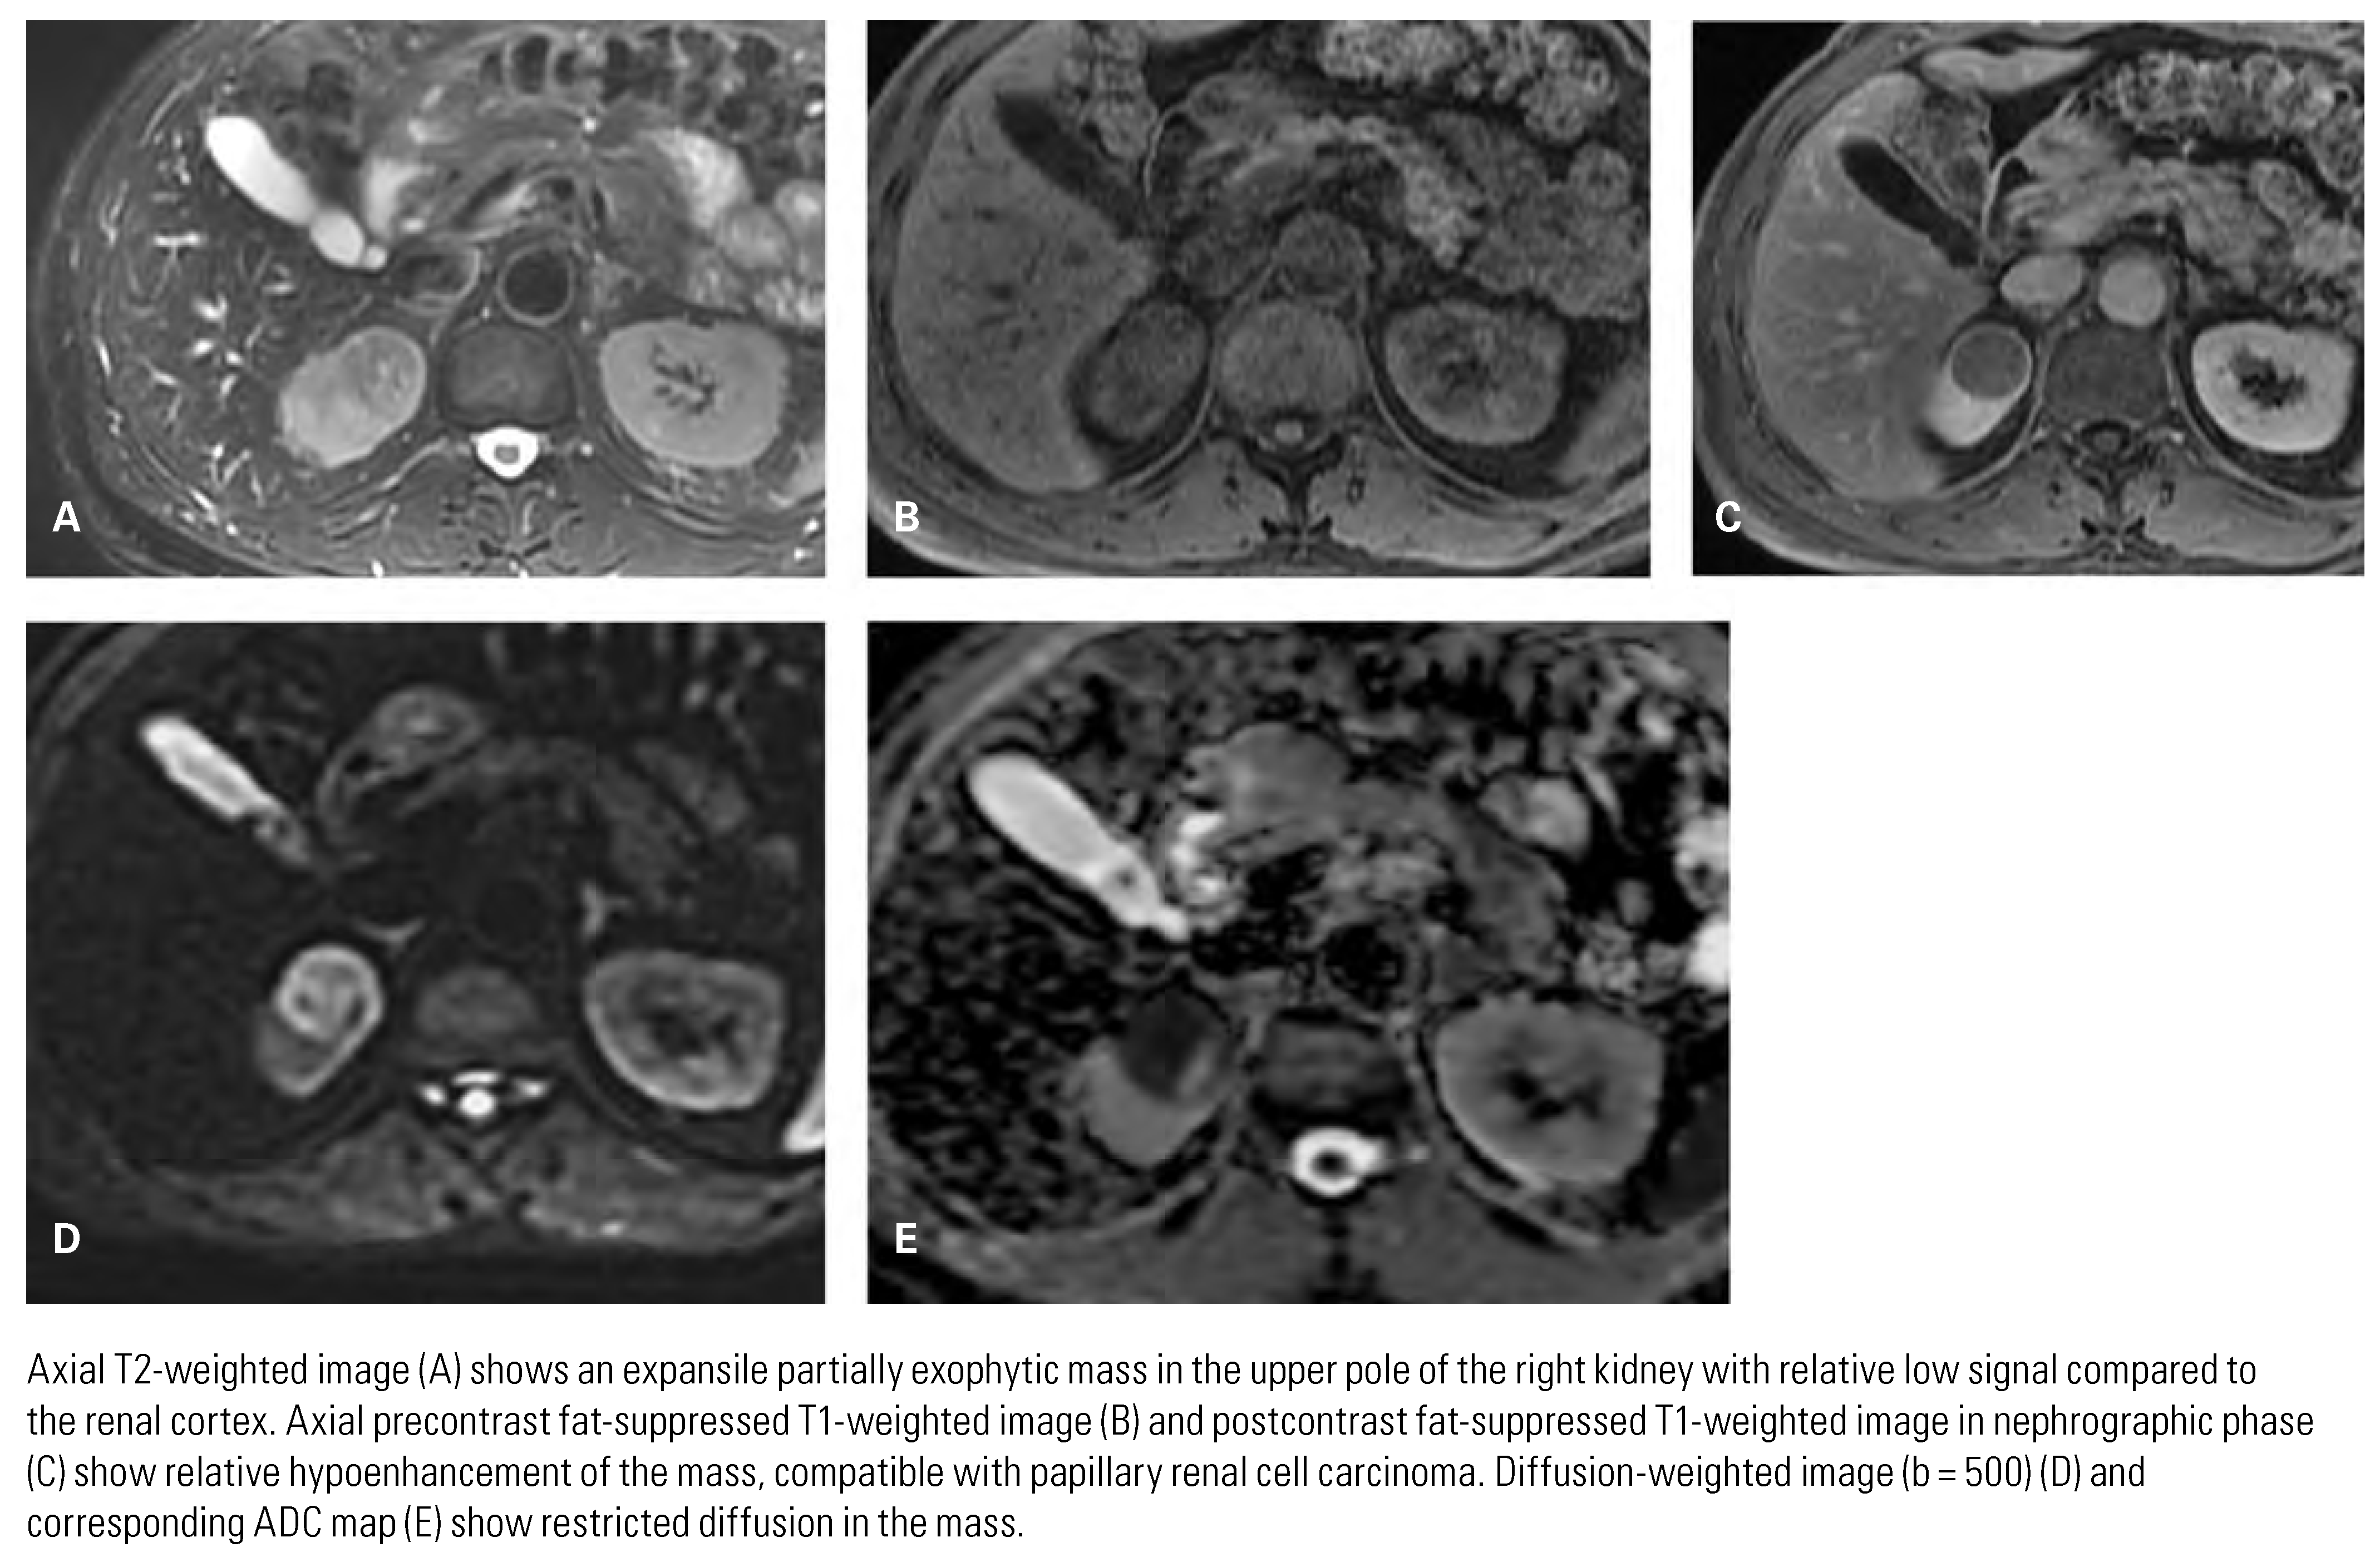

Papillary Renal Cell Carcinoma